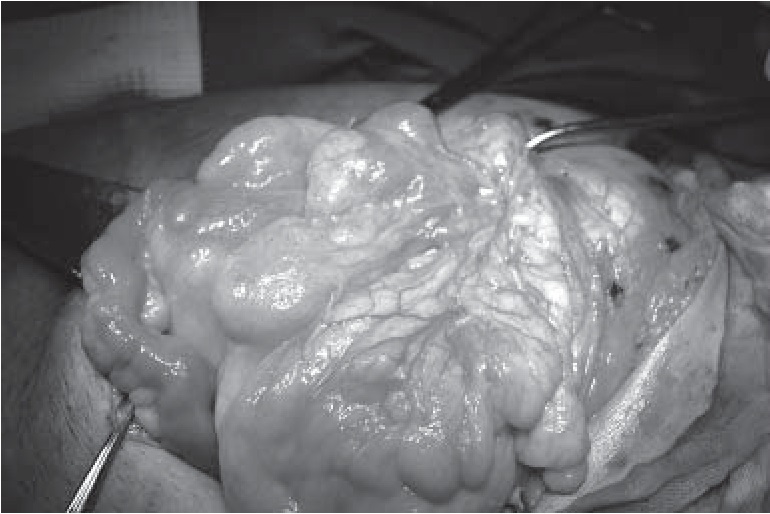

Выполнено иссечение избытка трофически измененной кожи грыжевого мешка, послойное ушивание послеоперационной раны с дренированием подкожно-жировой клетчатки по Редону. Окончательный вид послеоперационной раны и макропрепарата представлены на рисунке 4.

Рис. 4. Окончательный вид послеоперационной раны (а); макропрепарат, иссеченный избыток кожи с грыжевым мешком (б)